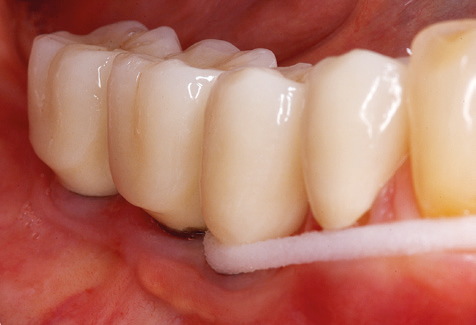

Nach der maschinellen Reinigung der Zahn­ und Implantatoberflächen erfolgt eine manuelle Instrumentierung der natürlichen Zahnoberflächen mit konventionellen Handinstrumenten. Bei der manuellen Reinigung ist insbesondere auf einen korrekten Anstellwinkel, eine ausreichende Schärfe, eine gute Abstützung und auf eine von apikal nach koronal gerichtete Arbeitsweise der Kürette zu achten. Zur Nachinstrumentierung der Implantatkonstruktionen sollten entweder Titan­ oder Carbonküretten verwendet werden (Abb. 8). Ergänzend zum Einsatz von Ultraschallgeräten können in der Erhaltungstherapie auch Pulverstrahlgeräte genutzt werden. Dabei ist jedoch zu berücksichtigen, dass diese Verfahren nicht zum Entfernen harter Beläge geeignet sind und daher die Verwendung von Hand­ oder Ultraschallinstrumenten nicht komplett ersetzen können. Abschließend erfolgt in jedem Fall eine mechanische Politur der zugänglichen Zahn­ und Implantatoberflächen mit Polierkelchen und Polierpasten (Abb. 9).

Abb. 9: Die Politur der zugänglichen Implantat­ und Zahnoberflächen erfolgt mit Polierkelchen und geeigneten Polierpasten. – Abb. 10: Die Reinstruktion zur Anwendung geeigneter Hilfsmittel bei der häuslichen Mundhygiene sollte ebenfalls Bestandteil der UPT sein. – Abb. 11a und b: Klinische Situation zwölf Jahre nach Insertion der prothetischen Versorgung. In diesem Zeitraum kam es lediglich zu einer Verblendkeramikfraktur am Zahn 47 und der Notwendigkeit einer endodontischen Behandlung am Zahn 12. Sämtliche Restaurationen sind noch in Funktion.